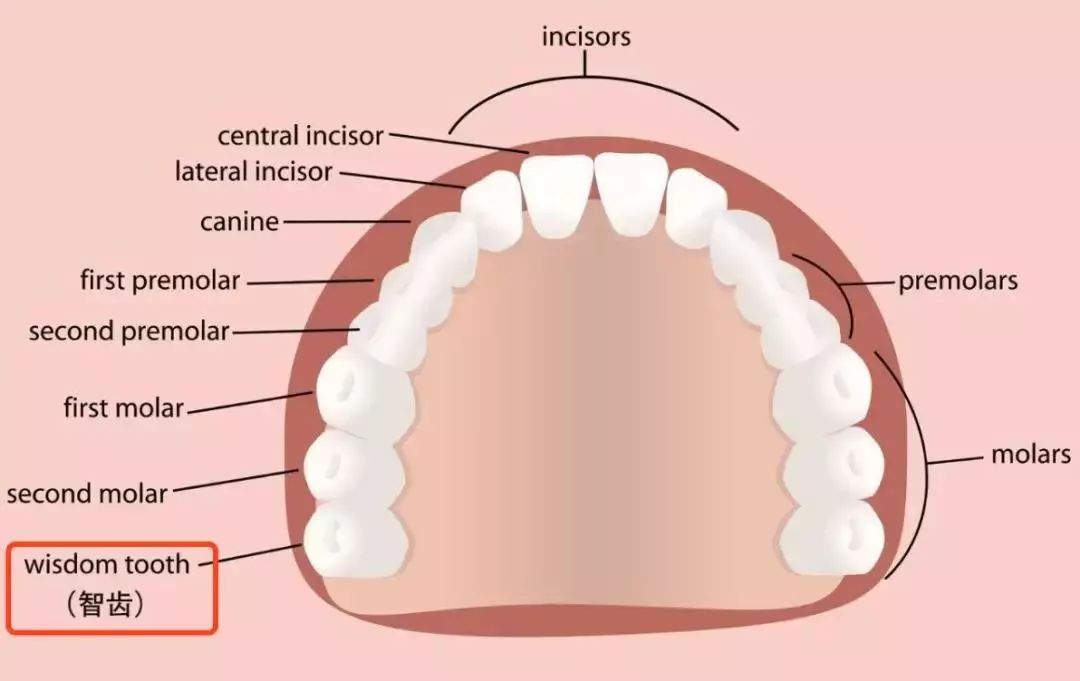

如果我们把正常成年人的口腔分为左上、左下、右上、右下四个区域的话,一般每个区域会有 8 个牙齿,长在最后的第 8 颗牙齿,就是传说中的「智齿」,也是我们的第三磨牙。

首先你对着镜子,先找到自己的中线位置。在两个门牙中间,就是中线位置。

然后尽可能张大你的嘴,从中线开始往两边数,门牙是第一个,数到第八个牙就是智齿。